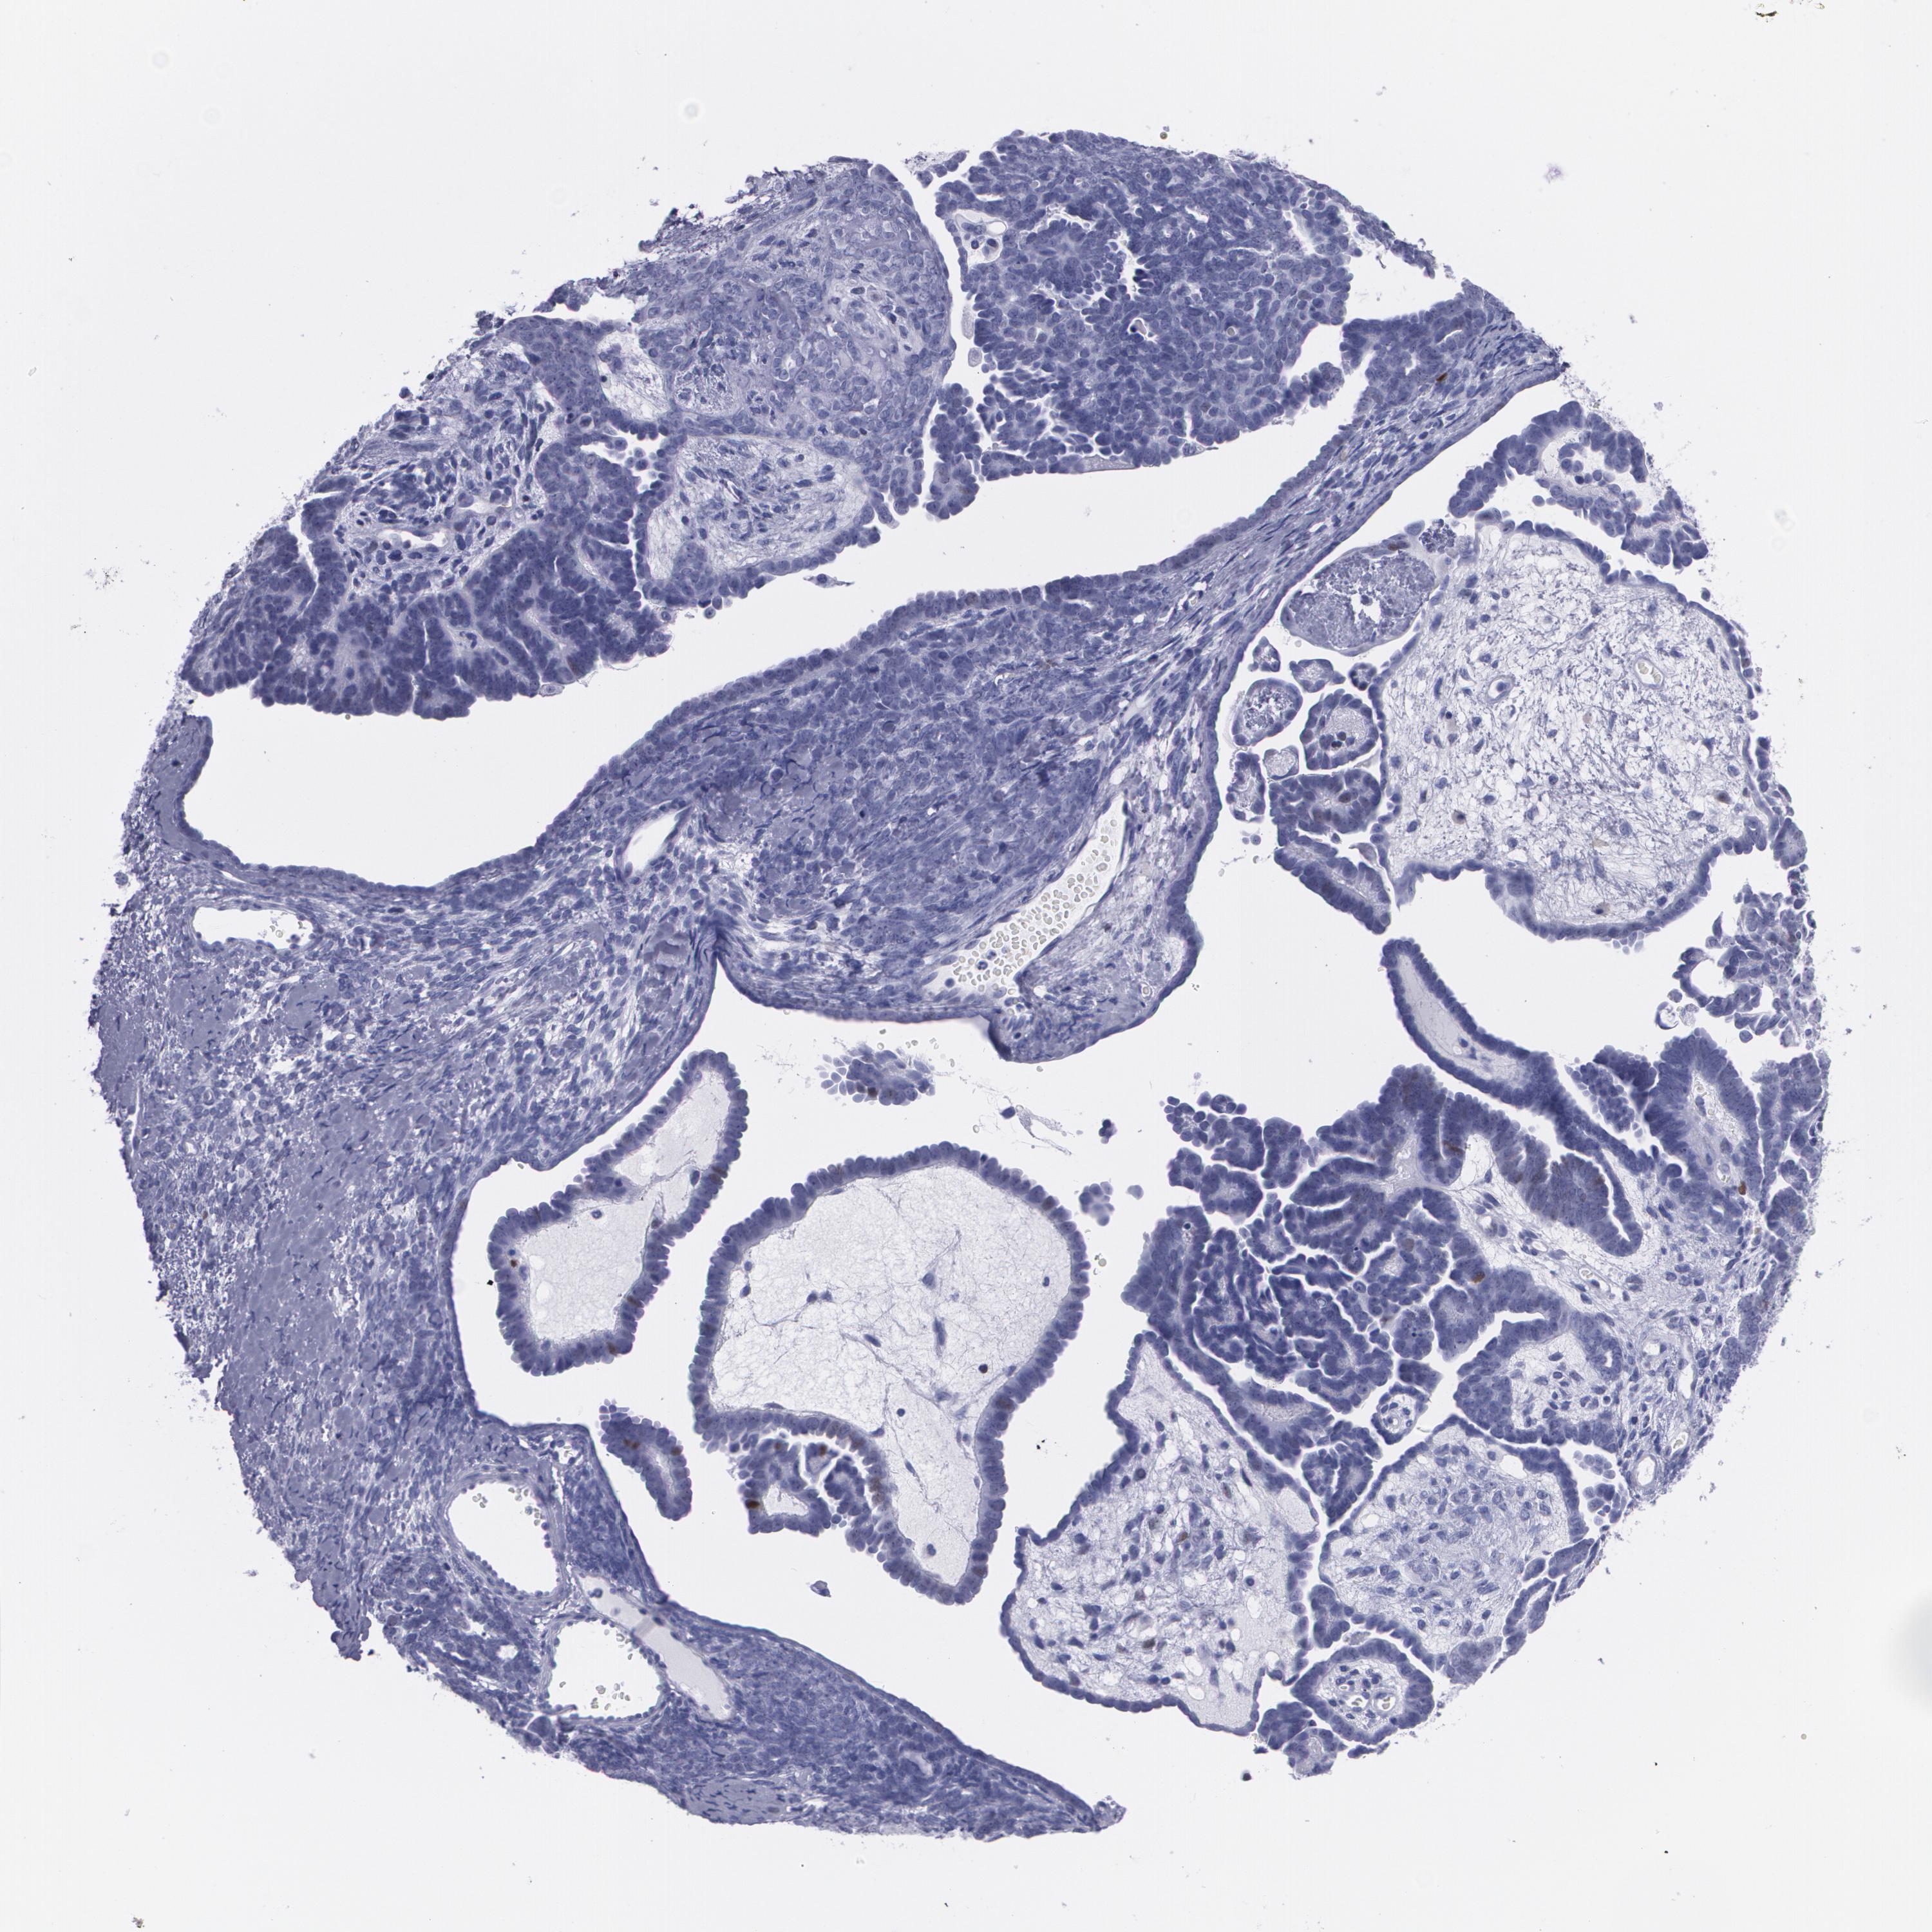

ENDOMETRIAL CANCER - Protein expressioni

A mouse-over function shows sample information and annotation data. Click on an image to view it in a full screen mode. Samples can be filtered based on level of antibody staining by selecting one or several of the following categories: high, medium, low and not detected. The assay and annotation is described here.

Note that samples used for immunohistochemistry by the Human Protein Atlas do not correspond to samples in the TCGA dataset.

Antibody stainingi

Antibody staining in the annotated cell types in the current human tissue is reported as not detected, low, medium, or high, based on conventional immunohistochemistry profiling in selected tissues. This score is based on the combination of the staining intensity and fraction of stained cells.

Each image is clickable and will lead to virtual microscopy that enables deeper exploration of all samples and also displays staining intensity scores, fraction scores and subcellular localization as well as patient and tissue information for each sample.

Antibody CAB002973

Antibody CAB039238

Antibody CAB039239

Antibody CAB072876

Staining

High

Medium

Low

Not detected

Intensity

Strong

Moderate

Weak

Negative

Quantity

>75%

75%-25%

<25%

None

Location

Nuclear

Cytoplasmic/membranous

Cytoplasmic/membranous,nuclear

Adenocarcinoma, NOS

Neoplasm, malignant, NOS

Adenocarcinoma, metastatic, NOS